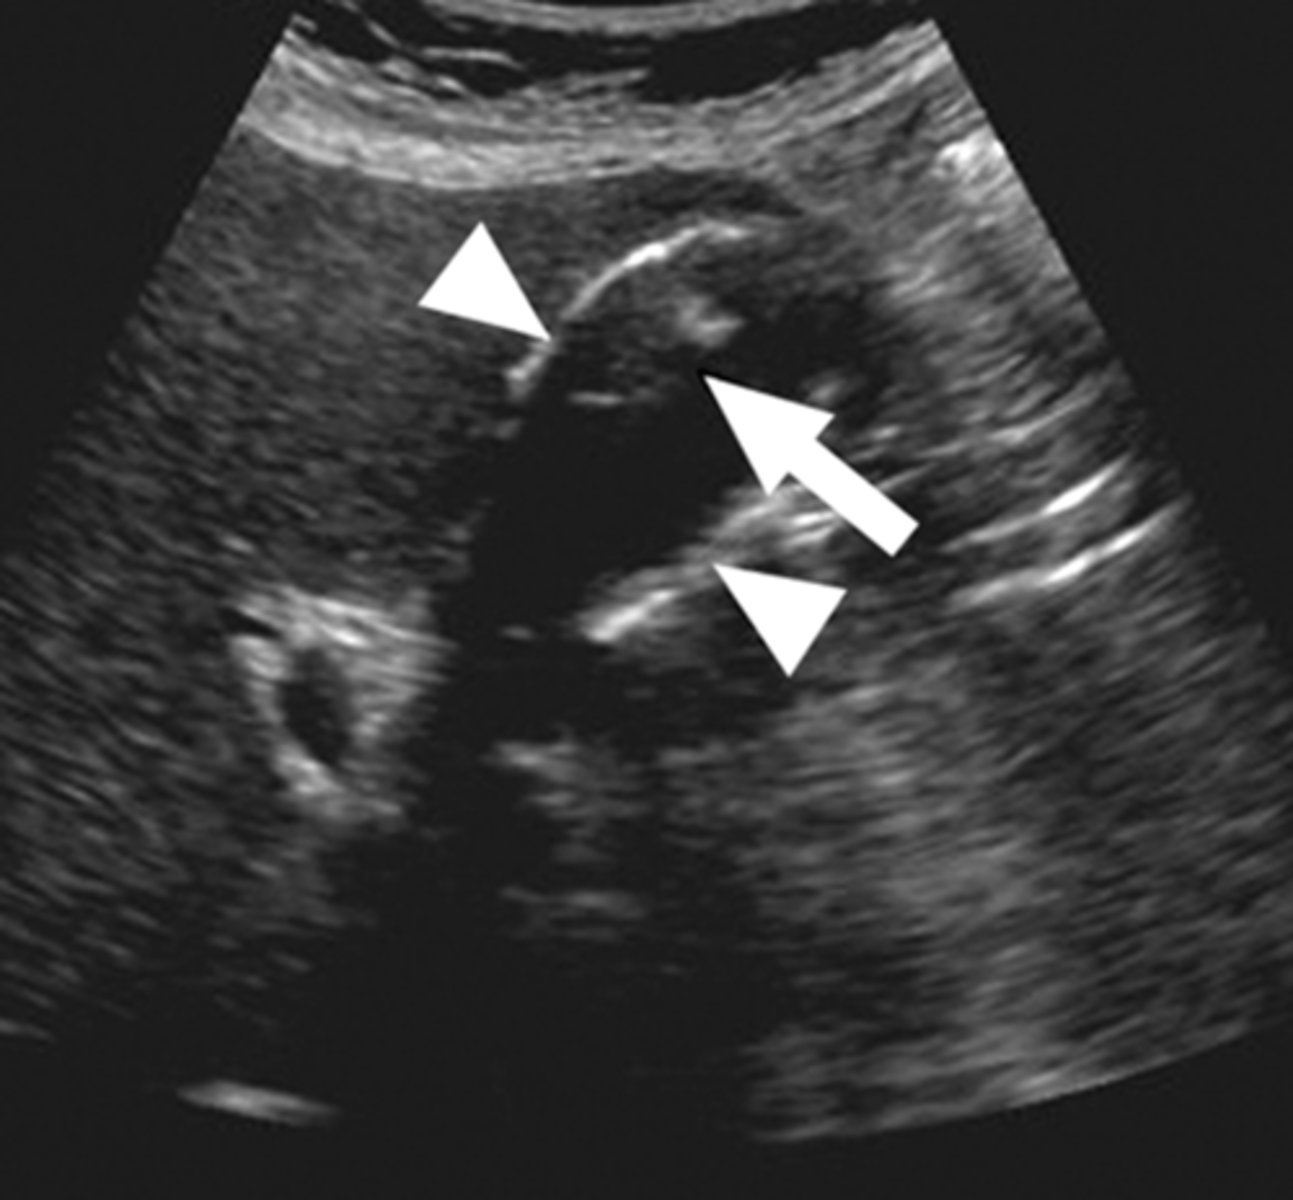

study of choice for abnormalities of biliary system

gallbladder US

gallstones

findings of acute cholecystitis

presence of gallstone (neck), thickening of gallbladder wall, fluid around gallbladder, positive murphy's sign

acute cholecystitis